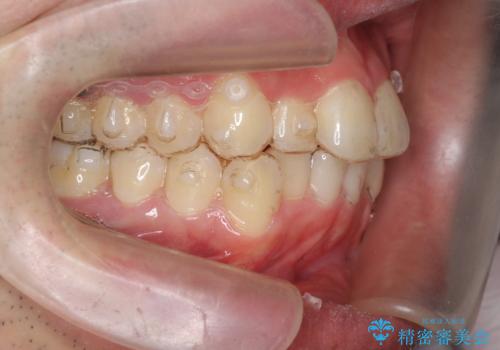

前歯のがたつき マウスピース矯正で 非抜歯で奥歯を後ろに下げる治療

- 前歯のがたつきを主訴に来院。

歯を抜かずに、奥歯を後ろに下げ、歯の両側をわずかに削って並べました。

奥歯を後ろに下げるのに、上下左右に矯正用ミニスクリューを入れています。

そのまま並べると戻りやすいのと、口元が出てしまうためです。

削る際も、拡大鏡を用いて精密に行っております。肉眼で削るのとは実は大きく差があります。

歯のがたつきがなくなると、歯ブラシがしやすくなり、茶色いステインも付きにくくなります。